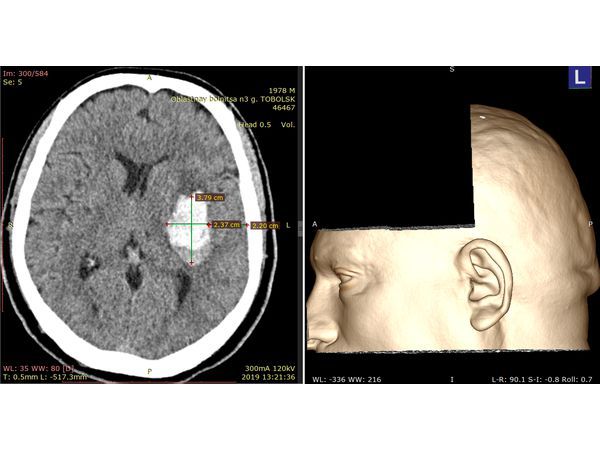

На КТ головного мозга в левой путаменально-капсулярной области выявлена инсульт-гематома.

С помощью бесплатной версии программы RadiAnt DICOM Viewer выполнена предоперационная разметка, т.е. намечен план операции.

Данный случай демонстрирует возможности бесплатной версии программы RadiAnt DICOM Viewer. Она позволяет планировать оперативный доступ на головном мозге. С её помощью был установлен размер гематомы и визуализирован доступ к ней.